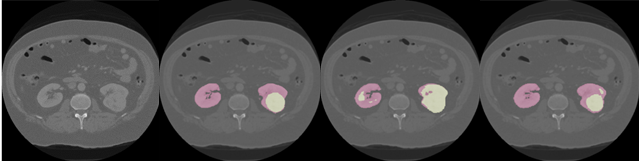

Figure 3: Example of a 66 year old patient from the test set in whom the cognizant sampling leveraging clinical characteristics improved segmentation of the cancer. From left to right: Image, ground truth annotations, segmentation from baseline 3D U-Net, segmentation from the model using cognizant sampling